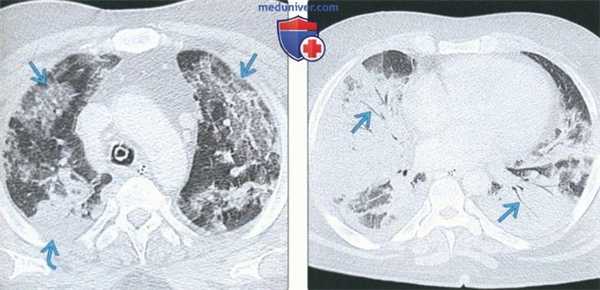

(Слева) На аксиальной КТВР у женщины 55 лет с интерстициальной пневмонией с аутоиммунными проявлениями визуализируются множественные участки «матового стекла» в обоих легких с апикально-базальным градиентом. Пациентка не отвечает ревматологическим критериям какого-либо аутоиммунного заболевания. Тем не менее, у нее обнаруживаются антинуклеарные и анти-EJ антитела.

(Справа) На аксиальной КТВР у этой же пациентки определяются двухсторонние участки «матового стекла» с преимущественным поражением базальных отделов, а также слабо выраженные тракционные бронхоэктазы. (Слева) На аксиальной КТВР у этой же пациентки в положении пациента лежа на животе сохраняются затемнения в виде «матового стекла» с преобладающей локализацией в базальных отделах.